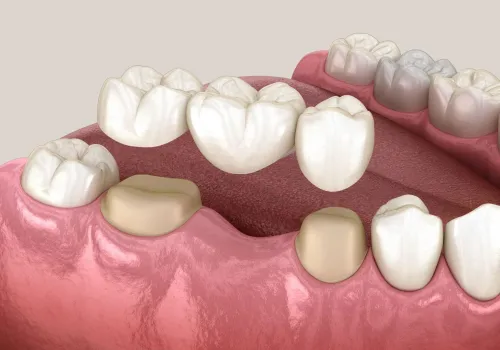

Der Vorteil des ALL-ON-4® Verfahrens liegt darin, dass mit nur 4 miteinander verbundenen Implantaten pro Kiefer eine festsitzende Brücke direkt nach dem Entfernen der nicht mehr erhaltungswürdigen Zähne eingesetzt werden kann. In der Regel kann auf eine provisorische Versorgung verzichtet werden, was dem Patienten erhebliche Kosten für den provisorischen Zahnersatz (ca. 1500 CHF pro Kiefer) spart.

Die auf den Implantaten verschraubten Brücken bestehen aus einem präzisionsgefertigten Titan- oder Vollkeramikgerüst und sind mit natürlich aussehenden Keramikzähnen ausgestattet.